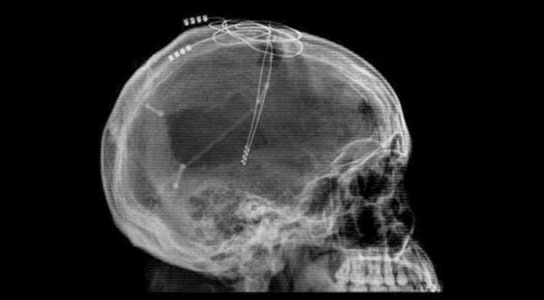

La intervención conlleva la perforación de orificios en el cráneo para implantar los cables a cada lado del trígono cerebral (fórnix), responsable de llevar la información al hipocampo –área del cerebro en la que se inician el aprendizaje y los recuerdos y donde, según asumen los científicos, se originan los primeros síntomas de la enfermedad de Alzheimer.

Los cables están conectados a un ‘estimulador’, un dispositivo similar a un marcapasos que genera 130 pequeños impulsos eléctricos por segundo en el cerebro. Y, como advierten los investigadores, «los pacientes no sienten la corriente«.